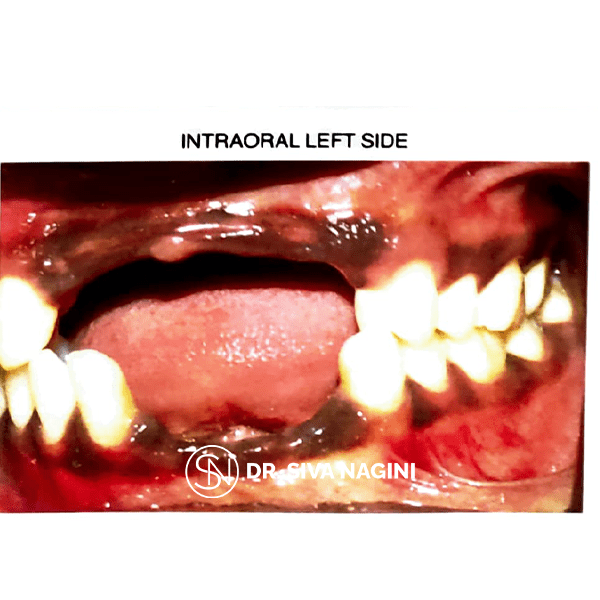

A 45-year-old male patient named Karimul has come to the department with the chief complaint of missing teeth in the upper and the lower anterior region for 4 months. The fixed partial denture was planned in both arches. Tooth preparation, cord packing and master impressions were done followed by cementation of the fixed partial prosthesis. High points were marked and corrected on periodic recall.